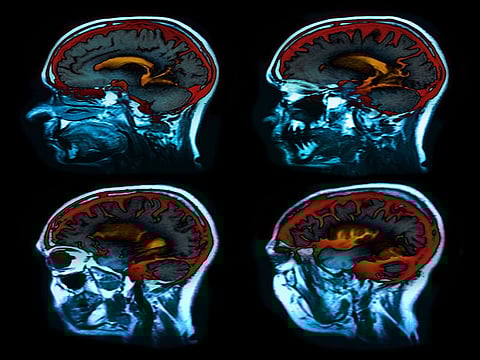

Entre 2016 y 2019, se realizaron escáneres cerebrales en un grupo de 68 hombres y mujeres de 46 a 80 años. El grupo incluyó a una variedad de pacientes, desde algunos que estaban mentalmente sanos a otros que tenían un deterioro cognitivo leve.

Los escáneres revelaron que las áreas del cerebro con un mayor número de ovillos de tau también presentaban una reducción en el flujo sanguíneo. Esto fue cierto en particular en un área del cerebro, conocida como "giro temporal inferior", que se cree que está entre las primeras regiones del cerebro donde se observa una acumulación de la tau en los cerebros de los pacientes con Alzheimer, incluso antes de que se hagan evidentes unas señales obvias de deterioro en el pensamiento.

Entonces, el equipo escudriñó datos de escáneres cerebrales recolectados entre 2017 y 2019 de un grupo distinto de 138 pacientes inscritos en la "Iniciativa de neuroimágenes de la enfermedad de Alzheimer". Los pacientes incluyeron a hombres y mujeres con diagnósticos que abarcaban desde el deterioro cognitivo leve hasta una demencia de Alzheimer en toda regla.

Una vez más, el equipo encontró que una reducción en el flujo sanguíneo cerebral se solapaba con un aumento en los ovillos en el cerebro.